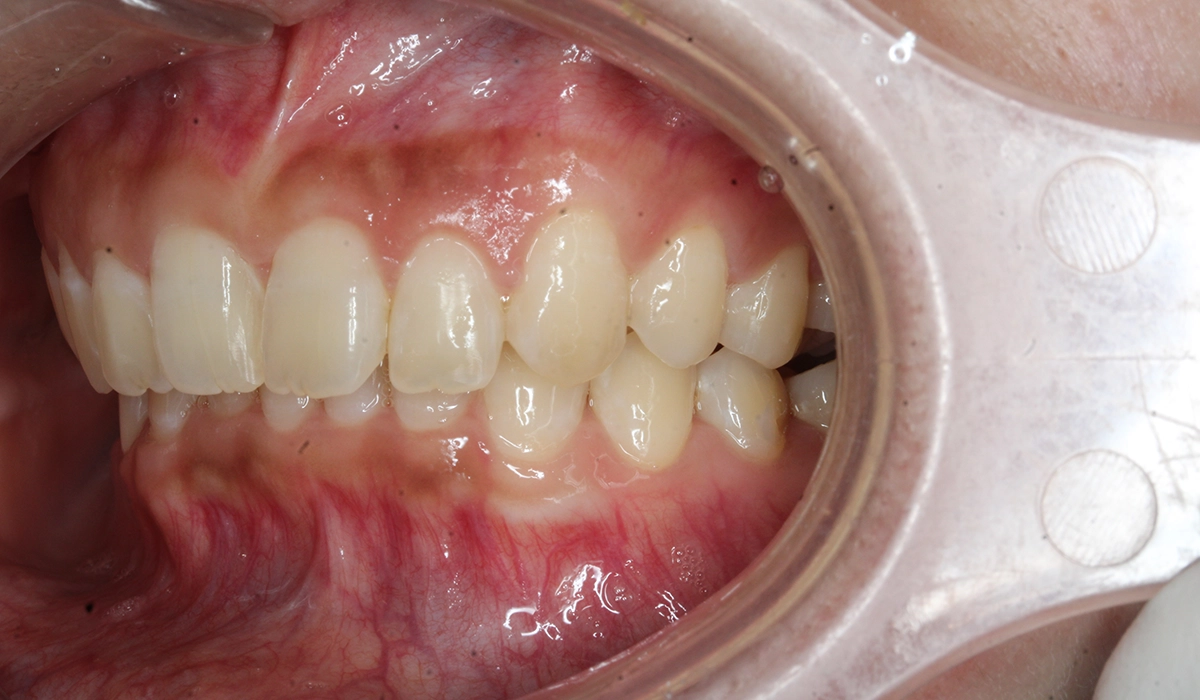

術前:左側

術後:左側